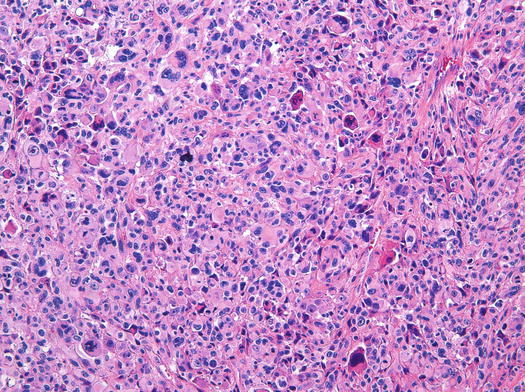

rhabdomyosarcoma alveolar power pathology low cells sarcoma tumor magnification fig abundant small high

Pathology Outlines - Alveolar Rhabdomyosarcoma

www.pathologyoutlines.com

www.pathologyoutlines.com

rhabdomyosarcoma alveolar pathology outlines leg